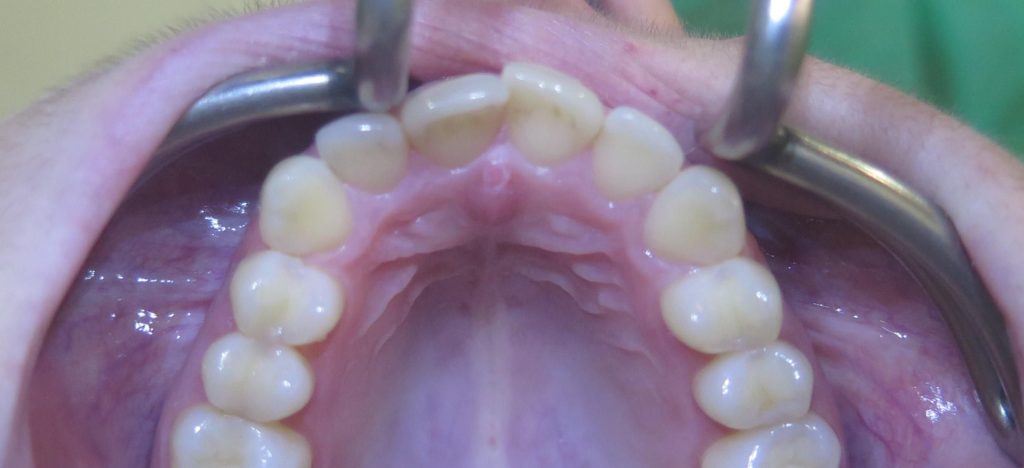

Przeprowadziliśmy precyzyjne leczenie implantologiczne, wszczepiając 11 implantów w szczęce i żuchwie. Konieczna była też regeneracja kości. Po 6 miesiącach gojenia nastąpiła odbudowa pełnołukowa. Kształt, kolor i ustawienie zębów zostały dobrane oraz wykonane na indywidualne życzenie Pacjenta.

Leczenie chirurgiczne i implanto-protetyczne przeprowadził lek.stom. Michał Badowski.

Następnie za pomocą nowoczesnych technologii cyfrowo zaprojektowaliśmy uśmiech, który Pan Bogdan mógł przymierzyć jeszcze przed rozpoczęciem właściwych zabiegów! Później została wykonana kompletna przebudowa zgryzu i uzupełnienie braków zębowych.

Pan Bogdan otrzymał nie tylko nowy uśmiech, ale zupełnie nowe życie!